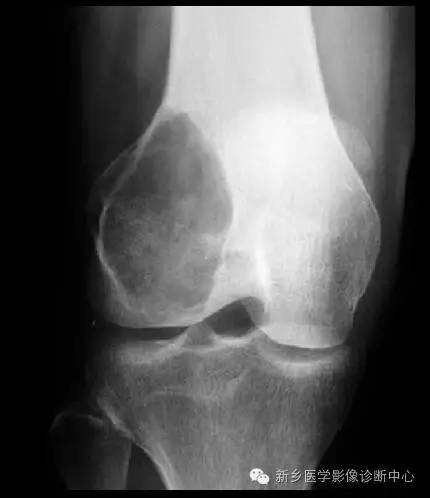

骨巨细胞瘤 起源于骨骼的非成骨性结缔组织,肿瘤的主要组成成分类似破骨细胞。肿瘤多见于15~30 岁的青壮年期,大多在骨骺愈合后,好发于股骨远端、胫骨近端及桡骨远端。早期仅有局部间歇性疼痛。常因肿瘤的发展,造成局部肿胀、压痛或邻近关节活动限制等。较大的肿瘤,可有局部皮肤温度增高、静脉曲张、压痛等症状。

1.巨细胞瘤虽开始于干骺端近骺板处,但几乎均越过骺板向关节方向生长,且以此为主,可直达关节软骨下为止。2.肿瘤大都局限于骨端和干骺端的松质骨内,并多向骨胳原来凸出的部分生长,使病区膨胀扩大,呈横向发展。其轮廓常呈分叶状,皮质虽变薄,但尚完整。其周围无骨膜反应亦无瘤组织肿块。无肿瘤基质钙化。3.肿瘤呈一与正常骨分界明显的密度减低区,其中可见类似多房间隔的残留骨小梁,明显时可呈"肥皂泡样"改变。4.在发病早期或进展期,其边缘可较模糊,中间如无似间隔的骨小梁,则诊断较困难,一般多根据病变部位而拟诊。5.病变晚期,肿瘤过度膨胀可使骨皮质破裂,且可侵入附近软组织中。

读片要点:1、多见于15~30 岁的青壮年期,大多在骨骺愈合后2、邻关节面生长,易向骨突部位发展3、长径与骨干垂直4、边缘多无高密度硬化或更模糊5、骨性间隔较细6、几乎没有骨膜反应和钙化,无成骨现象